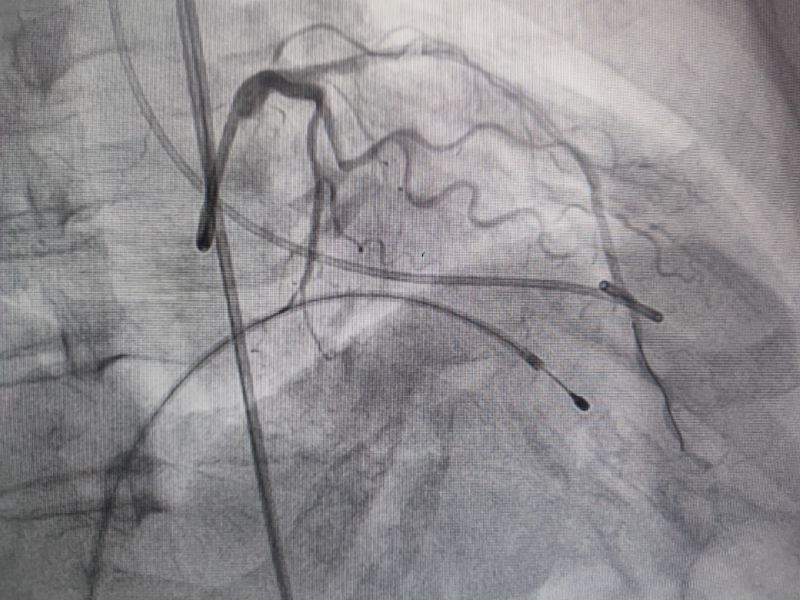

冠脉造影

经过多轮严谨的术前讨论,在吴栋梁院长的专业指导下,崔旭辉主任医师团队决定在临时起搏器的安全保护下,为患者实施冠状动脉造影术及室间隔化学消融术。术中,团队通过造影精准锁定第一穿隔支为消融靶血管。测压数据显示:左室压260/15mmHg,流出道173/6mmHg,主动脉压106/70 mmHg,压力阶差达87mmHg。随后,团队使用2.0X15mm预扩球囊以8atm压力阻断第一穿隔支远端血流1分钟,再次测压时,压力从269/7mmHg骤降至174/4mmHg,这一结果充分证实该血管正是室间隔的有效供血血管。紧接着,团队通过SPRINTER OTW2.0×8mm球囊缓慢注入1.4ml无水酒精。10分钟后复测,左心室压降至136/5 mmHg,主动脉压为112/93 mmHg。术后第2天,王女士胸闷、气短、心悸等不适症状完全消失。复查心脏彩超显示:EF值与FS值保持稳定,收缩期左室流出道血流速度降至252cm/s,PG值为25mmHg。